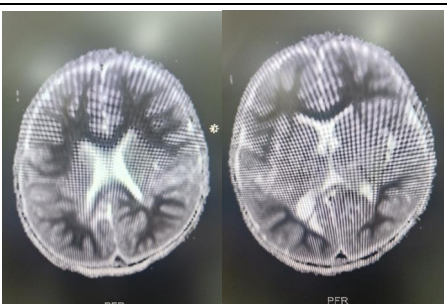

2 year old boy presented to Medanta, the medicity with history of fever, loose stools since 3 days and posturing  since last 1 day. Admitted outside, loaded with levetiracetam, phenytoin and valproate and sent to medanta in view of persistent posturing. The child was intubated in view of poor GCS and started on midazolam infusion and later Ketamine infusion was added. Seizures controlled clinically and EEG also confirmed the same. MRI Brain done s/o- symmetrical diffusion restriction involving the bilateral frontoparietal, periventricular and deep white matter with no grey matter involvement s/o ALERD . CSF study was suggestive of- normal biochemistry  2 cells with negative PCR .The child was given IVIG and pulse methyl prednisolone in view of inflammatory pathology. Autoimmune enphalitis work up was negative. The  child improved gradually , extubated and discharged.

Fig 1, 2:  MR images showing diffusion restriction in Bilateral symmetrical periventricular and deep white matter.

Figure 1